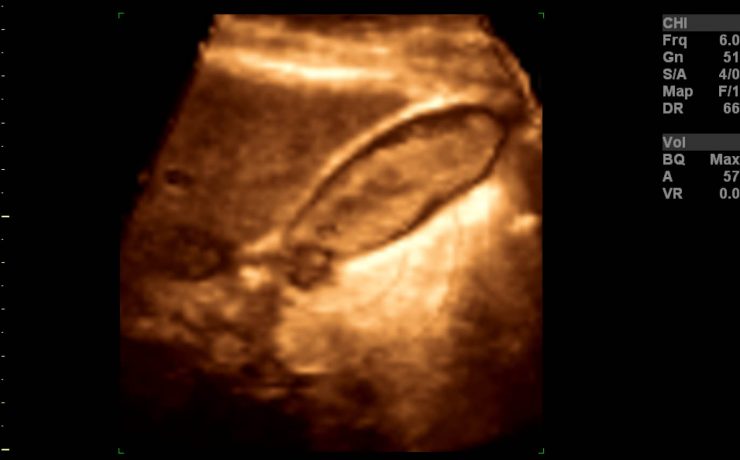

Marcadores ultrasonograficos para enfermedades genéticas

El síndrome de Down es una malformación congénita causada por una alteración del cromosoma 21 (trisomía del par 21) que se acompaña de retraso mental moderado o grave. Debe su nombre a John Langdon Haydon Down quién fue el primero que describió esta condición en 1866, Las personas con